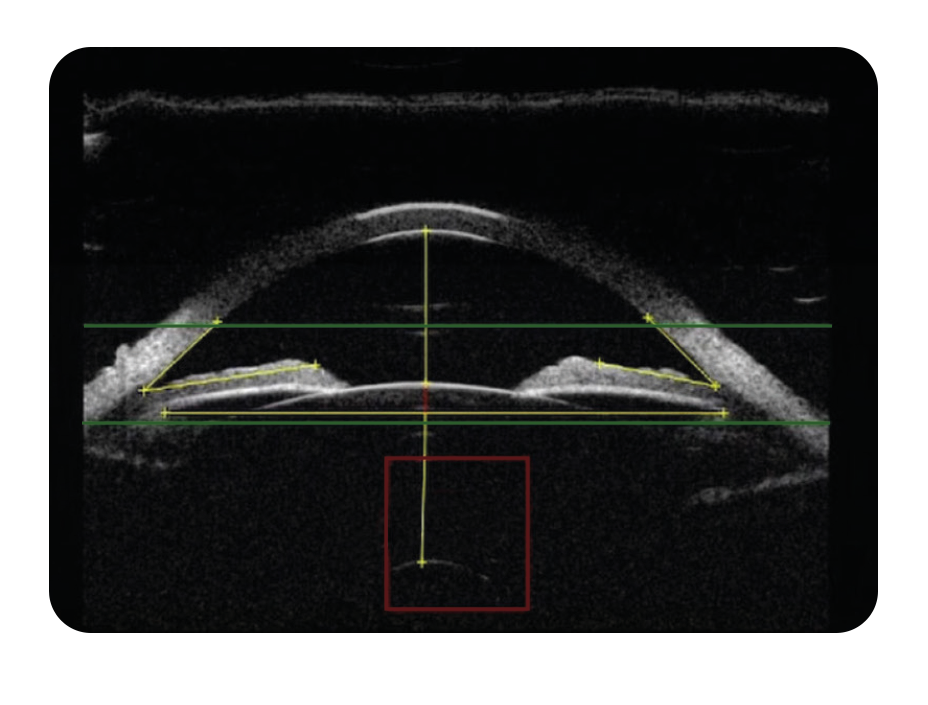

The ABSolu’s high-resolution UBM imaging provides crystal-clear view of the anterior segment.

With outstanding axial and lateral resolution, every ocular structure — from iris to ciliary body — is sharply defined.

Better image quality means more accurate STS visualization and greater confidence when selecting the optimal ICL size.

Its true perpendicularity ensures highly reproducible images of the anterior segment, delivering precise and consistent Sulcus-to-Sulcus images — the foundation for successful ICL sizing.

- Capture Sulcus-to-Sulcus (STS) images with the ABSolu using the exclusive linear 50 MHz UBM probe.